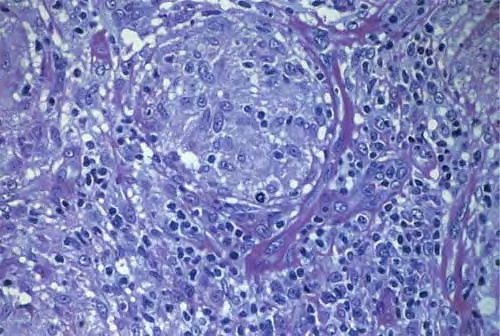

Lupus vulgaris = ุงูุฐุฃุจ ุงูุดุงุฆุน Lupus Vulgaris LV is an extremely chronic, progressive form of cutaneous tuberculosis occurring in individuals with moderate immunity and a high degree of tuberculin sensitivity. Differential Diagnosis of Tuberculosis Verrucosa Cutis ยท Warts or keratoses ยท Hyperkeratotic lupus vulgaris ยท Blastomycosis ยท Chromomycosis ยท Bromoderma ยท Lesions due to […]